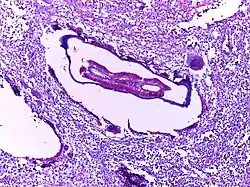

![]() |

Helminth in appendix | Micrograph showing lumen of appendix and cut section of pin worm. | Category: Histopathology of appendix with Enterobius vermicularis | Parasitic helminthiasis infectious disease |